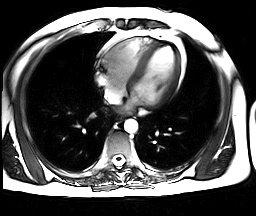

Esta técnica utiliza ultra-som e o efeito Doppler para medir o débito cardíaco. A velocidade do sangue através da aorta causa um “desvio Doppler” na freqüência de retorno das ondas de ultra-som.

A medida pela ecocardiografia da superfície de corte do arco aórtico (ou, alternativamente, dá área da aorta descendente), combinada com a velocidade de fluxo, permite o cálculo do débito cardíaco.